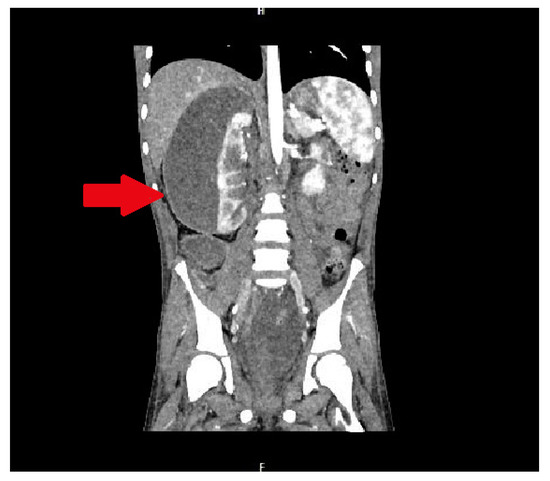

In the infectious disease ward, COVID-19 was excluded. During hospitalization, the patient developed acute abdominal symptoms. The acute condition of the boy appeared suddenly. Results of laboratory tests showed deviations in white blood cells (WBC) = 11.89 × 103/µL, and hemoglobin (HGB) = 6.9 g/dL, with hematocrit (HCT) = 20.6%. The inflammatory markers were elevated. Urinalysis showed 75 mg/dL of proteins. The ultrasound of the abdomen and computed tomography were performed. The diagnosis was unclear. Inflammation, abscess, cyst, and abdominal tumor were suggested. In the computed tomography (CT), the lesion had dimensions: 11.1 × 8.2 × 25 cm (Figure 1 and Figure 2).

Figure 1. The lesion of unknown character in the area of the right kidney, shown in the transverse plane of the CT scan. The lesion is marked by an arrow.